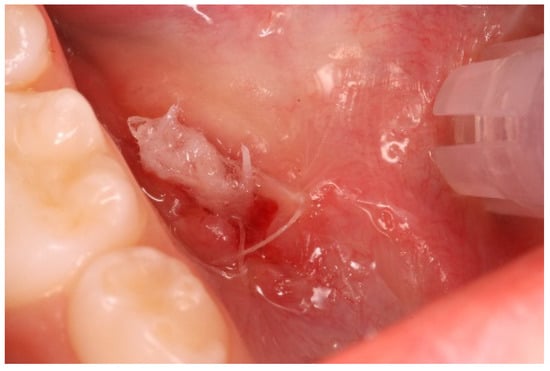

- Anesthesia. Premedication with topical anesthesia (Xylonor Spray—10% lidocaine analgesic solution; Septodont) was followed by infiltration with mepivacaine (Pierrel S.p.A. mepivacaine 20 mg/mL and adrenaline 1:100,000) around the margins of the lesion.

- Incision. Soft tissue incisions with microsurgical scissors to remove the pseudocystic dome and provide adequate access to the area of interest.

- Probing and irrigation. The lumen of the lesion was probed, irrigated with sterile saline solution, and dried with cotton gauze.

- Application of Hybenx®. Hybenx® gel was injected into the lumen of the lesion. The choice of gel was based on its consistency to avoid dispersion of the product into the surrounding tissues. The gel (0.5 mL) was allowed to act for approximately 20 s and then aspirated, and the area was rinsed with copious amounts of saline solution. After complete and careful gel removal, the lesion margins appeared opaque white, with no signs of bleeding.

- Suturing. To delay closure of the ostium and inversion of the margins of the lesion, horizontal mattress sutures (6-0 coated Vicryl® undyed 1 × 18″ s-14 double armed—Ethicon®) were performed to evert the wound edges and keep the ostium open (Figure 5).